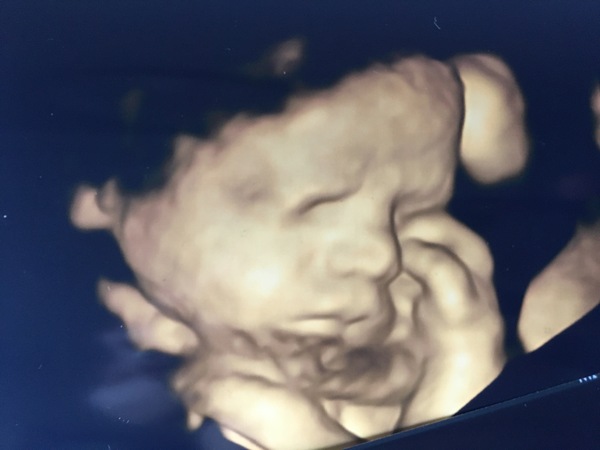

We had a 3D scan today, which I was really excited for! All was good, but I kinda feel a bit deflated now. My husband found the whole thing really stressful and triggering which I wasn’t expecting and it was really tough to see him struggling. Baby boy had been moving so much the hours before my scan he must’ve got comfy, and wasn’t in the best place to see his face and the woman jokingly said ‘he’s not moving much is he he must be cosy’. They sent me off for a walk and husband was very quiet. When I asked what was wrong, he replies ‘well he’s not moving, so it’s happening again’... he didn’t realise that babies do have sleep times where they don’t move as much and thought that, like when lily stopped moving permanently, that something was wrong. 😭 bless him. I did explain and when we went back in baby boy had flipped around so we could see his little face, and I could literally see my husband relax. Pleased he was rheee and that he did get to see him, but just didn’t think of how triggering and stressful scans must be for him especially when he can’t feel all the movements I do!

@Anon20something gorgeous scan picture of your boy! I'm sorry to hear that your DH had suck a tough time, blokes tend to do such a good job of being "ok" that it's easy to forget they don't get the same constant reassurance that we do once we're getting used as a trampoline/football pitch.

@Anon20something look at his little hand up to his face!!!

@Anon20something that’s a lovely picture although hard about your DH, I can imagine mine would have been similar in the circumstances